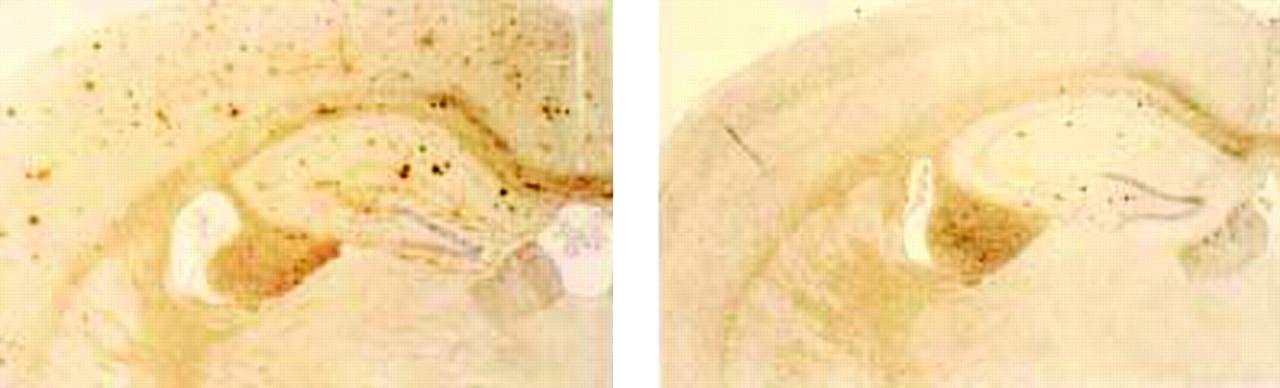

Lack of murine apoE dramatically reduces the amount of Aβ/amyloid burden even in very old transgenic mice. Numerous thioflavine S-fluorescent (A) as well as Aβ immunoreactive deposits (C) are evident in both the cortex and hippocampus of transgenic mice that express the V717F mutant of the amyloid precursor protein as well as apoE, but is dramatically reduced when apoE is absent (B, D). Adapted from (42).